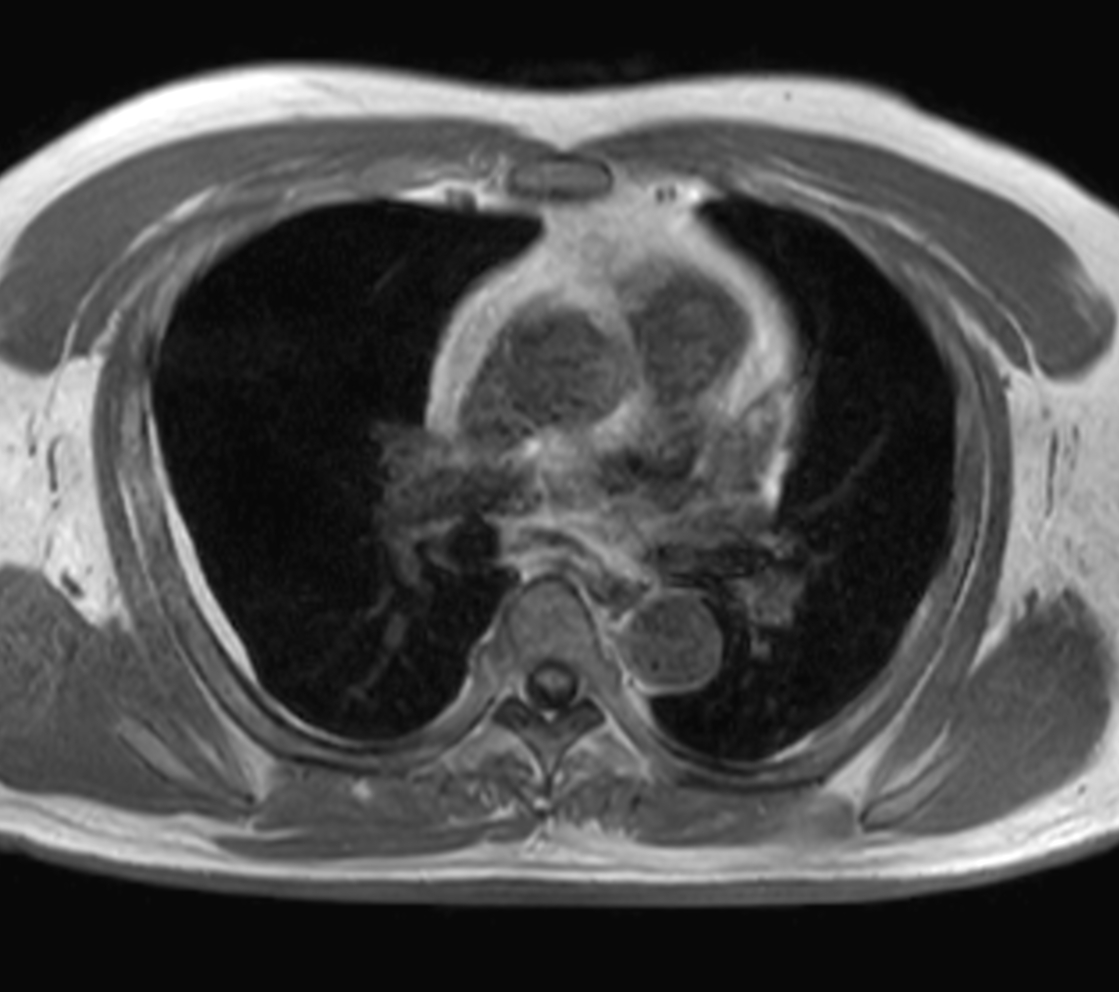

Axial T2w TSE - Black Blood

Axial T2w STIR - Black Blood

Axial MultiVane XD - T2w SPIR